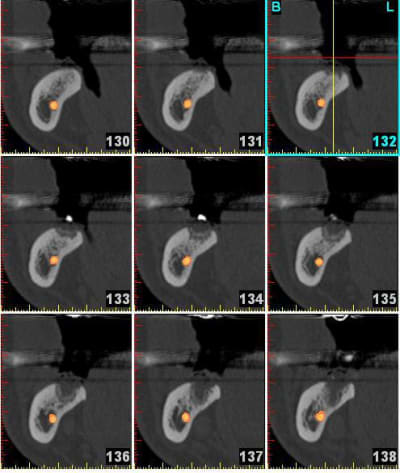

voici le cas extraction en décembre 2011 ce qui me pose problème c'est le 2eme implant le 8 mm passe mais le col ne serait pas enfoui , ne vaut il donc pas mieux plus enfouir un 6 mm d'où ma question.

L'os dans le 2 eme site est type 4 et type 3 vers le fond et avec le 8 mm je me retrouve dans la corticale linguale

Mes premiers implants courts: Que des implants courts! Pas assez de recul (2 ans) de plus on voit que celui en 27 n'a pas été enfoui j'ai laissé le col dépassé ( voulait pas qui parte dans le trou trou).

A toi de voir si ça t'aide. Ok je n'avais pas de contrainte d'axe prothétique (grace au système)mais bon ça renseigne un peu.

sinon le deuxième site, moi, me paraît louche...c'est pas du D4, j'aurais plutôt tendance à dire que c'est du tissu de granulation...( et peut être bien un petit morceau de racine...c'est pas très net...)

une racine le morceau en distal e je l'ai enleve avant le scan, la radio date du 21.1 et le scan du 14.3.... je ne pense pas avoir de pano d'ensemble post extractionnel.

oui, donc tu es à 8 semaines post extraction pour ton scan...c'est un peu juste pour juger de la densité osseuse, non?

le problème: tu es limite en hauteur, et si tu es dans du mou, çà va pas vraiment le faire pour trouver une stab primaire...

perso, je laisserais çà tranquille encore 1 mois ou 2, pano de contrôle et si ok, on plante...

et non pas à 8 semaines je l'ai extraite le 19.11.2011 donc c'est plus et je te joins une retro avant l'extraction la dent ne présentais pas de lésion paro enorme donc je ne vois pas pourquoi un TG se serait développé plus facilement.

à 4 mois amha çà devrait être plus dense si tout était normal...

A mon avis aussi et maintenant quelles solutions mis à part un implant court ou une greffe qui a des chance de rater (les 2 que j'ai fais faire n'ont pas pris) et les exclusifs sur Marseille (qui font partie des pointures nationales) préfèrent de leur avis des implants court (7mm chez Nobel) plutôt que des greffes.

a mon avis, sur la 2eme zone d'implant, t'es dans de la soupe! tu vas au casse-pipe si tu plantes...(j'ai déjà eu ce genre d'image et conclusion...)

la lacune semble bien délimitée par des parois, donc tu peux tenter: ouverture curetage et comblement.